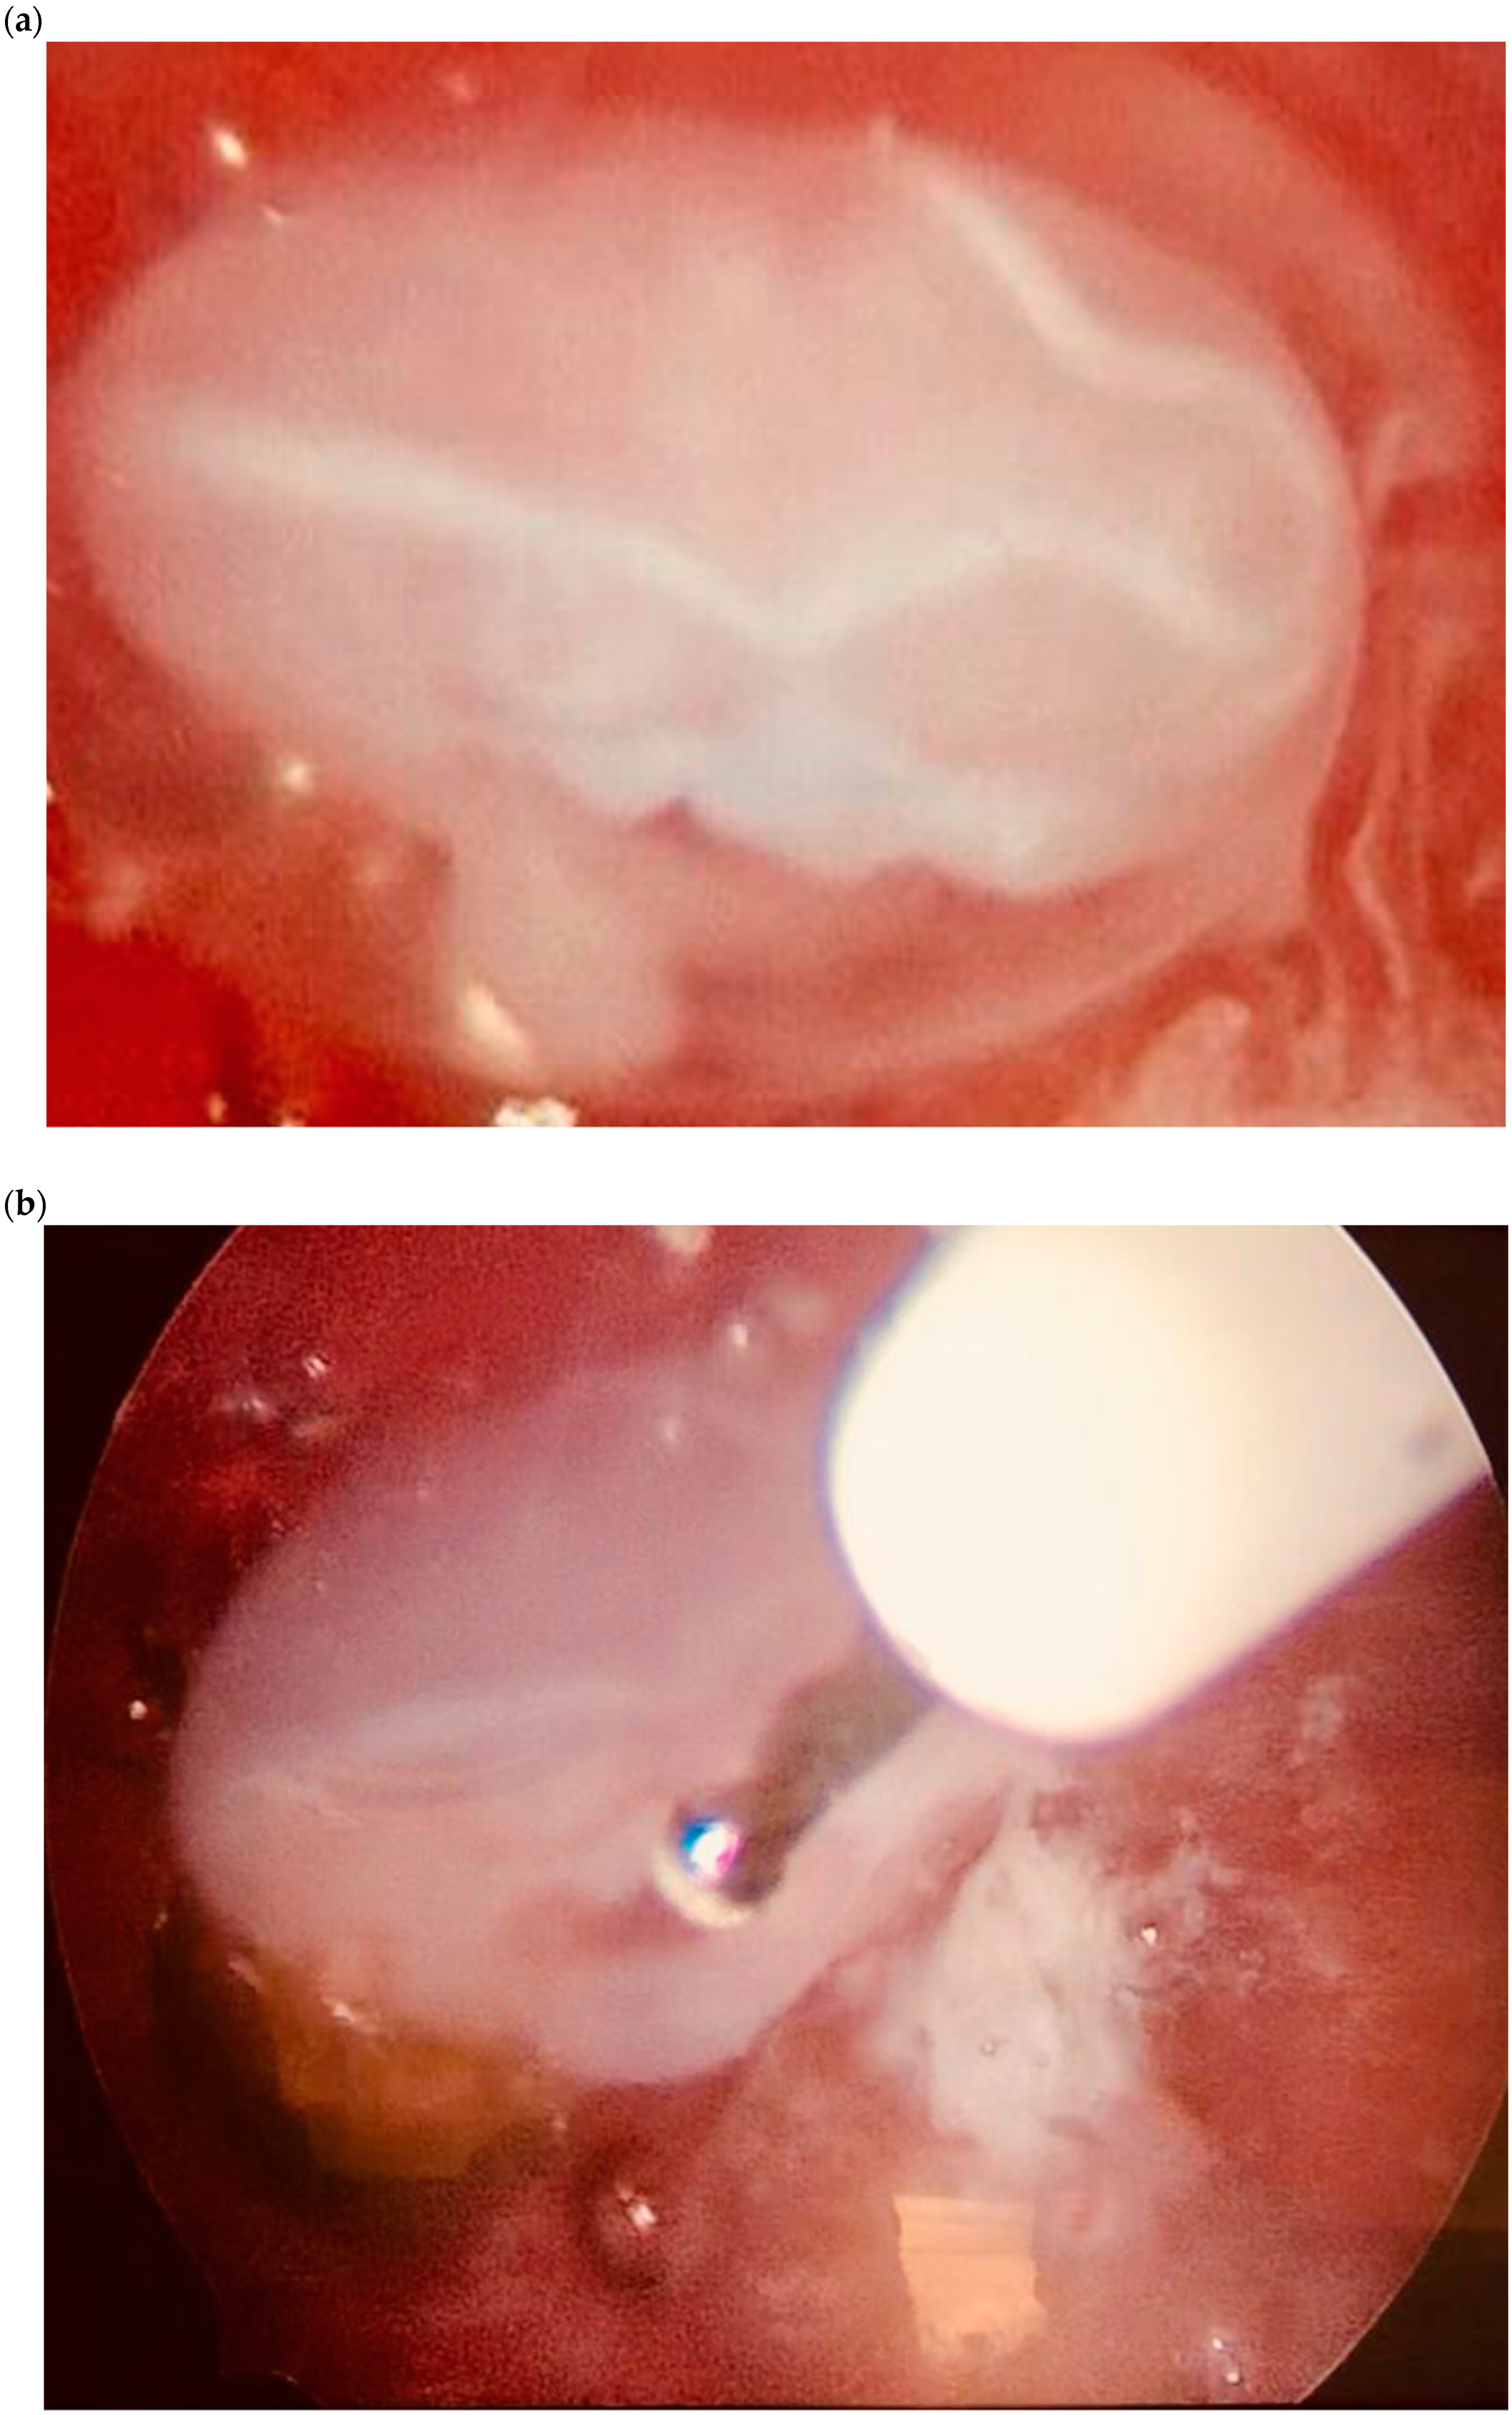

| Case 2 | Asymptomatic | 6 + 6 | 10,862 | GS 20 × 19 mm; with embryo | Hys: 1st step: CP resection by twizzle; IC Foley catheter 2nd step: vessels electrocoagulation by bipolar twizzle | Reoperation (hys) due to tissue residues and cervical laceration Complete resolution |

| Case 3 | Asymptomatic | 5 | 9747 | GS 20 × 22 mm; no embryo | MTX IM 50 mg/m2 of body surface + Hys | Complete resolution Currently pregnant (PMA Homologous) |

| Case 4 | Brownish vaginal discharge | 6 + 6 | 55,951 | GS 30 × 10 mm; no embryo | Hys | Complete resolution |

| Case 6 | Vaginal bleeding | 6 | 4274 | GS 5.4 × 5 mm with embryo | MTX IM 50 mg/m2 of body surface + Hys: CP resection by twizzle | Complete resolution |